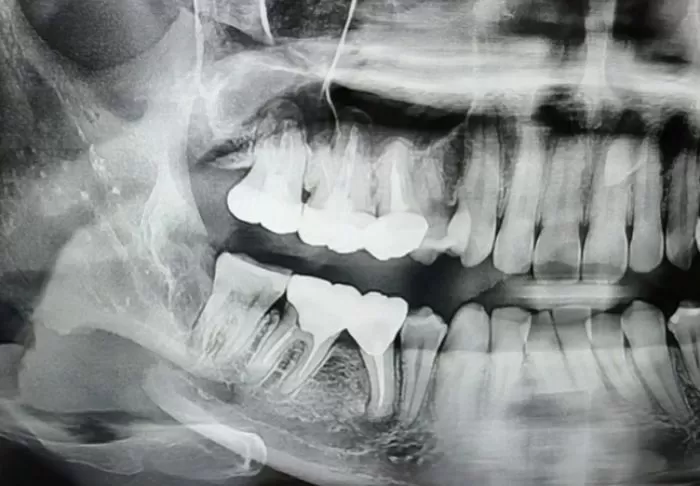

A씨는 발치 후 입을 다물 수 없을 정도로 끔찍한 고통을 느꼈고 결국 턱뼈 엑스레이를 찍어 상태를 확인했다.

충격적이게도 A씨의 오른쪽 아래턱뼈가 부러져있었다. 그러나 의료사고를 낸 치과 측은 이를 확인한 후에도 별다른 조치를 취하지 않았다.